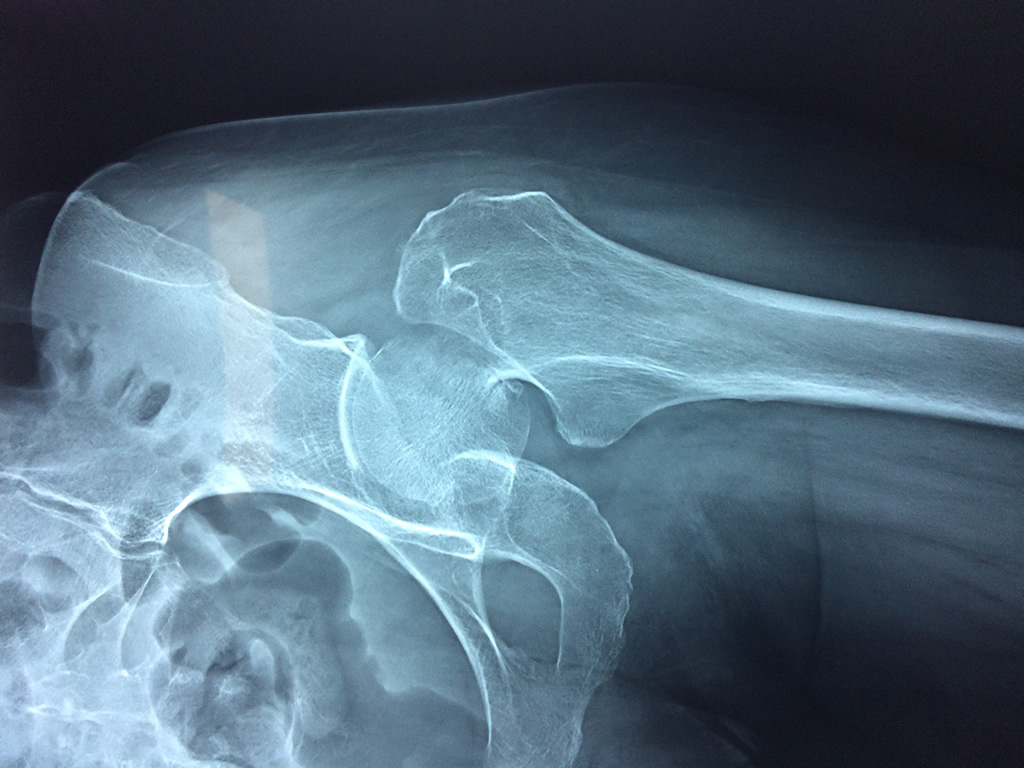

La cirugía de fractura de cadera se realiza para reparar una ruptura en la parte superior del hueso del muslo. Este hueso se denomina fémur.

Es parte de la articulación coxofemoral. Si una fractura de cadera no recibe tratamiento, es posible que deba permanecer en una silla o en la cama.

A menudo se recomienda la cirugía para reparar la fractura debido a dichos riesgos.